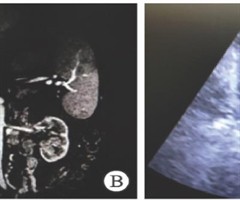

术中经食管超声发现肾癌癌栓进展而临时变更手术方案1例报告

DOI:10.3969/j.issn.1009-8291. 2025.09.016 肾癌具有向静脉系统侵袭的特性, 4%~10% 的肾癌患者合并下腔静脉癌栓, 1% 的患者合并右心房癌栓[1]。临床上常用梅奥(Mayo)分级系统根据癌栓顶端...